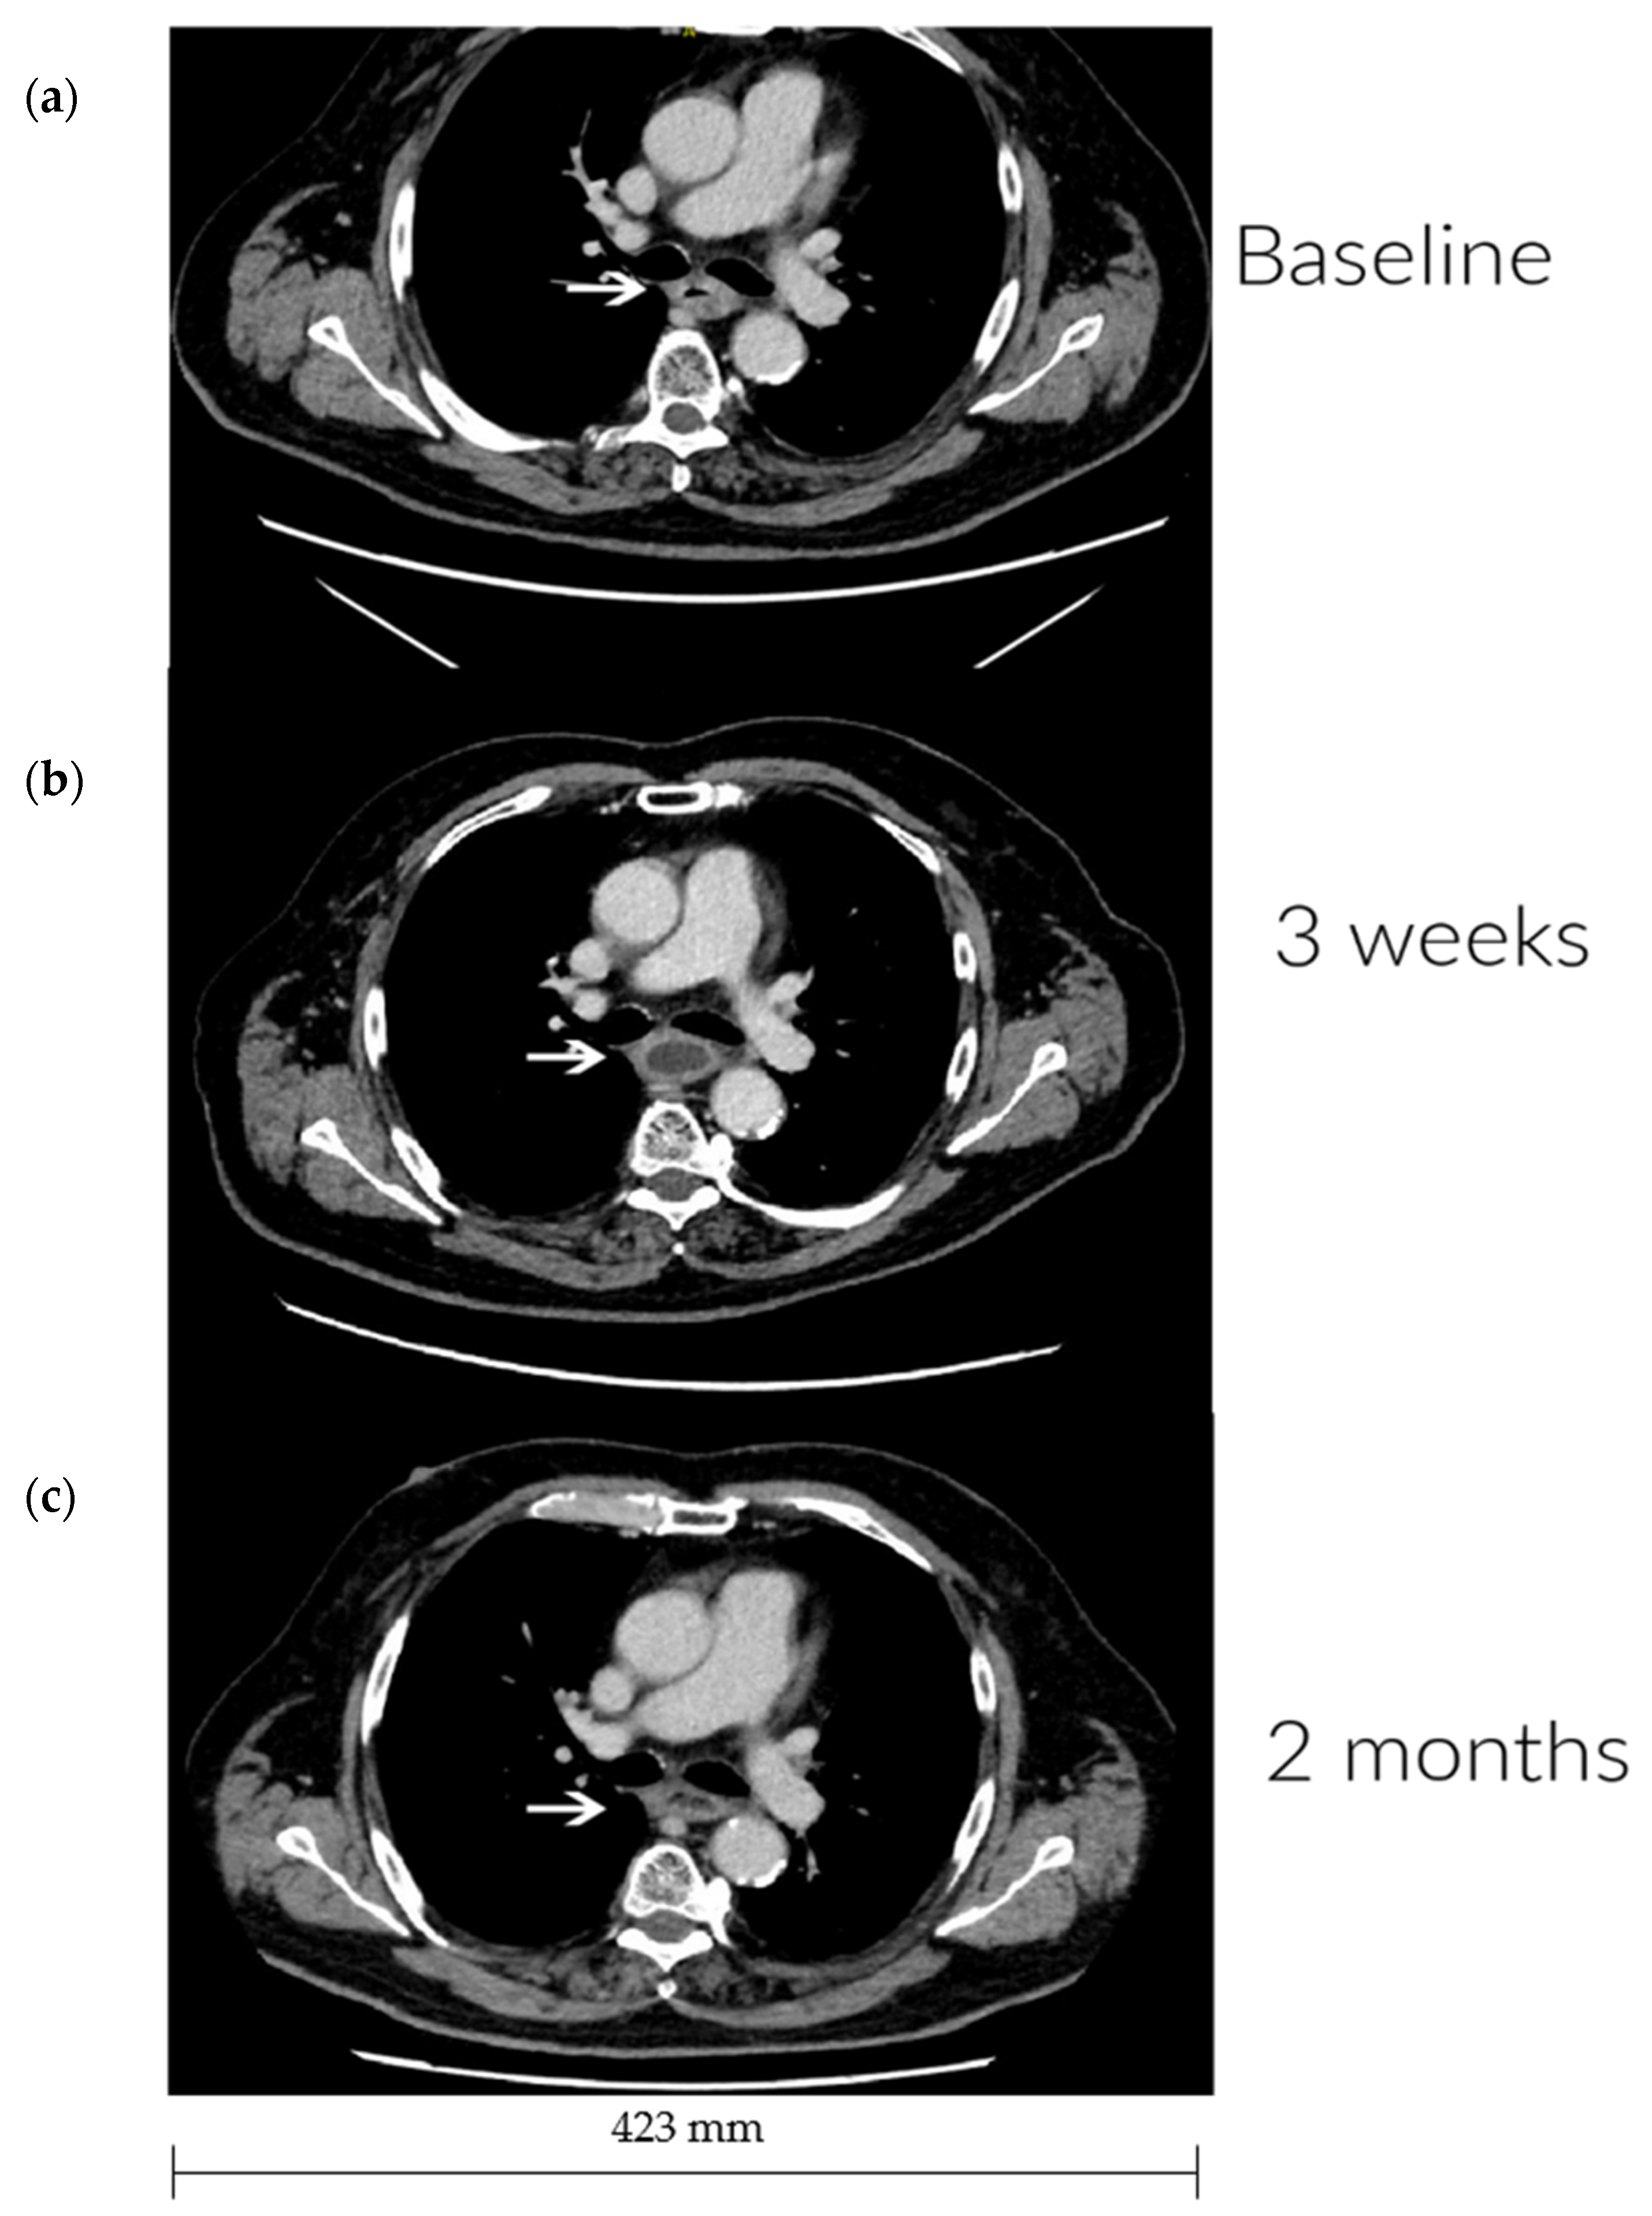

All patients underwent a baseline CT scan and a minimum of one additional evaluation CT. From the evaluation CT, it was observed that one patient had a partial tumor response (Figure 2), three patients had stable disease, and four patients had tumor progression during the follow-up period. No response in distant metastases was seen.

Figure 2.

Imaging response. CT imaging at (a) baseline, (b) three weeks, and (c) two months after treatment. The arrows indicate the tumor localization in the thoracic part of the esophagus. (a) Largest esophageal wall thickness is 10 mm. A left main bronchial impression is seen due to tumor size. (b) Diminishing circumferential wall thickness corresponding to the treated area. The bronchial impression is no longer observed. (c) No further changes, stable disease.